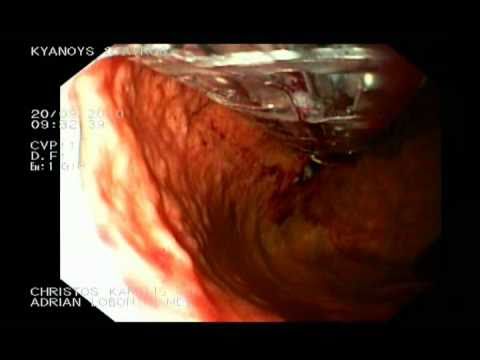

Rak Trzustki W Badaniu EUS - Stadium T4.

Poniższy materiał wideo przestawia raka trzustki (stadium T4) w badaniu EUS.